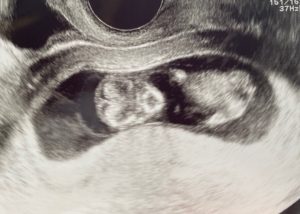

(8w1d CRL14.2mm)

健診でのエコーのおかげです。

こんなにつらくても赤ちゃんは元気に育ってくれてるんだと思って

(10w2d CRL41mm)